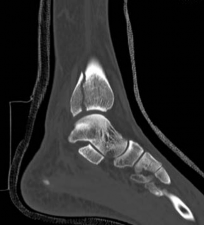

Standard orthogonal radiographs (anteroposterior and lateral) are sufficient for initial diagnosis, but they routinely underestimate the complexity of partial articular fractures. A high-resolution computed tomography (CT) scan with two-dimensional multiplanar reformats (coronal and sagittal) and three-dimensional surface rendering is considered the standard of care.

CT imaging is critical for:

1. Identifying the exact location and size of the articular fragments.

2. Detecting central articular depression that is obscured by the cortical rim on plain films.

3. Mapping fracture lines extending into the diaphysis.

4. Planning the surgical approach to ensure direct access to the primary fracture line.

Image